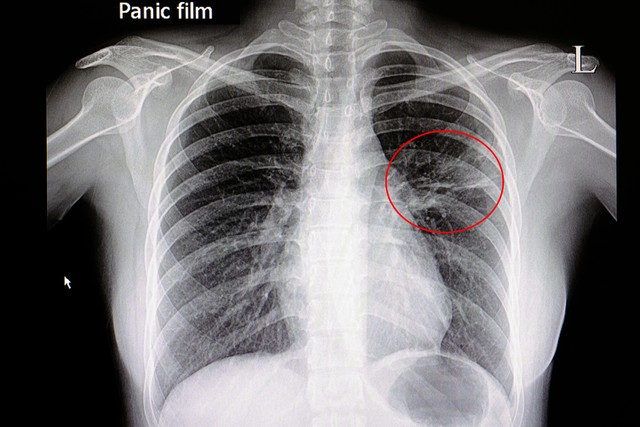

肺炎